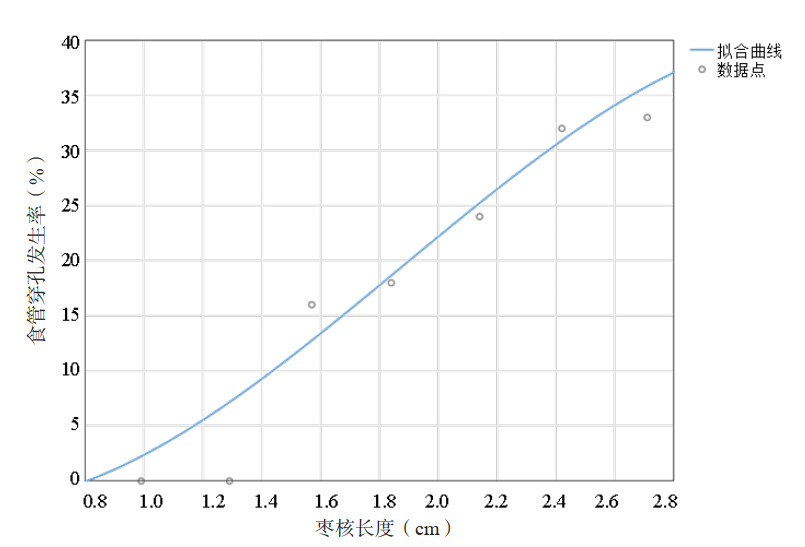

在145例患者样本中,食管嵌顿枣核长度分布在0.89~2.85 cm范围内。每0.3 cm为一段将数据分为7分段,分别计算每段的枣核长度均值,并根据公式(1)计算每段内患者的穿孔发生率,见表 3。

利用双平方最小二乘法对表 3数据进行拟合分析,得到如下公式:

其中L表示枣核长度,PL表示食管穿孔的预测概率。拟合曲线见图 3,拟合优度RL2=0.93,均方根误差RMSEL=0.050。

| 图 3 枣核长度和食管穿孔发生率的曲线拟合 |

经研究枣核长度、枣核长轴与食管壁夹角均为食管穿孔的危险因素,分别与食管穿孔发生的概率呈一定规律。由公式2可知食管嵌顿枣核长度和发生食管穿孔的概率符合三次多项式模型(RL2=0.93)。由图 3可知穿孔的发生率随枣核长度的增长而增长。由公式3可知枣核与食管夹角的角度和发生食管穿孔的概率符合Logistic模型(RD2=0.96)。由图 4的拟合曲线可知,夹角在40°以内几乎不会发生食管穿孔,40°~70°范围内穿孔发生率随夹角增大而增长,超过70°后维持30%以上的高发生率。值得注意,数据点(39.3°,6.0%)的残差较大(δ=0.057),是由于在37°~45°范围内收集的17例患者中,有1例枣核长轴与食管壁夹角为40°的患者发生了食管穿孔。因此结合拟合曲线和数据点,可将35°设置为低风险临界值,当枣核与食管壁的夹角小于35°时发生穿孔风险较低。70°设置为高风险临界值,当夹角大于70°时发生穿孔的风险较高,应引起足够重视。对于枣核与食管壁夹角在35°~70°范围内的情况,可以参考枣核长度与食管穿孔发生率的关系(公式2)做出进一步判断。